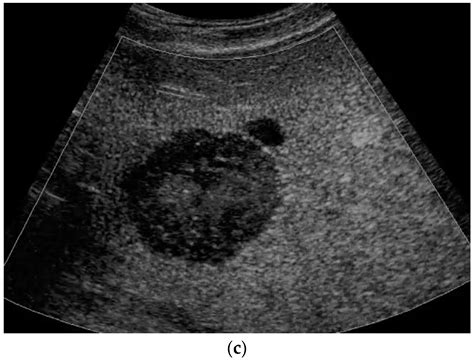

• Hemangiomas: These are the most common type of benign liver tumor, consisting of a tangle of blood vessels. They are usually small and rarely cause symptoms.

Common Types of Benign Liver Lesions

The vast majority of findings categorized as a lesion on liver are benign. These are typically growths that do not cause significant symptoms and are often discovered by chance. Common types include: